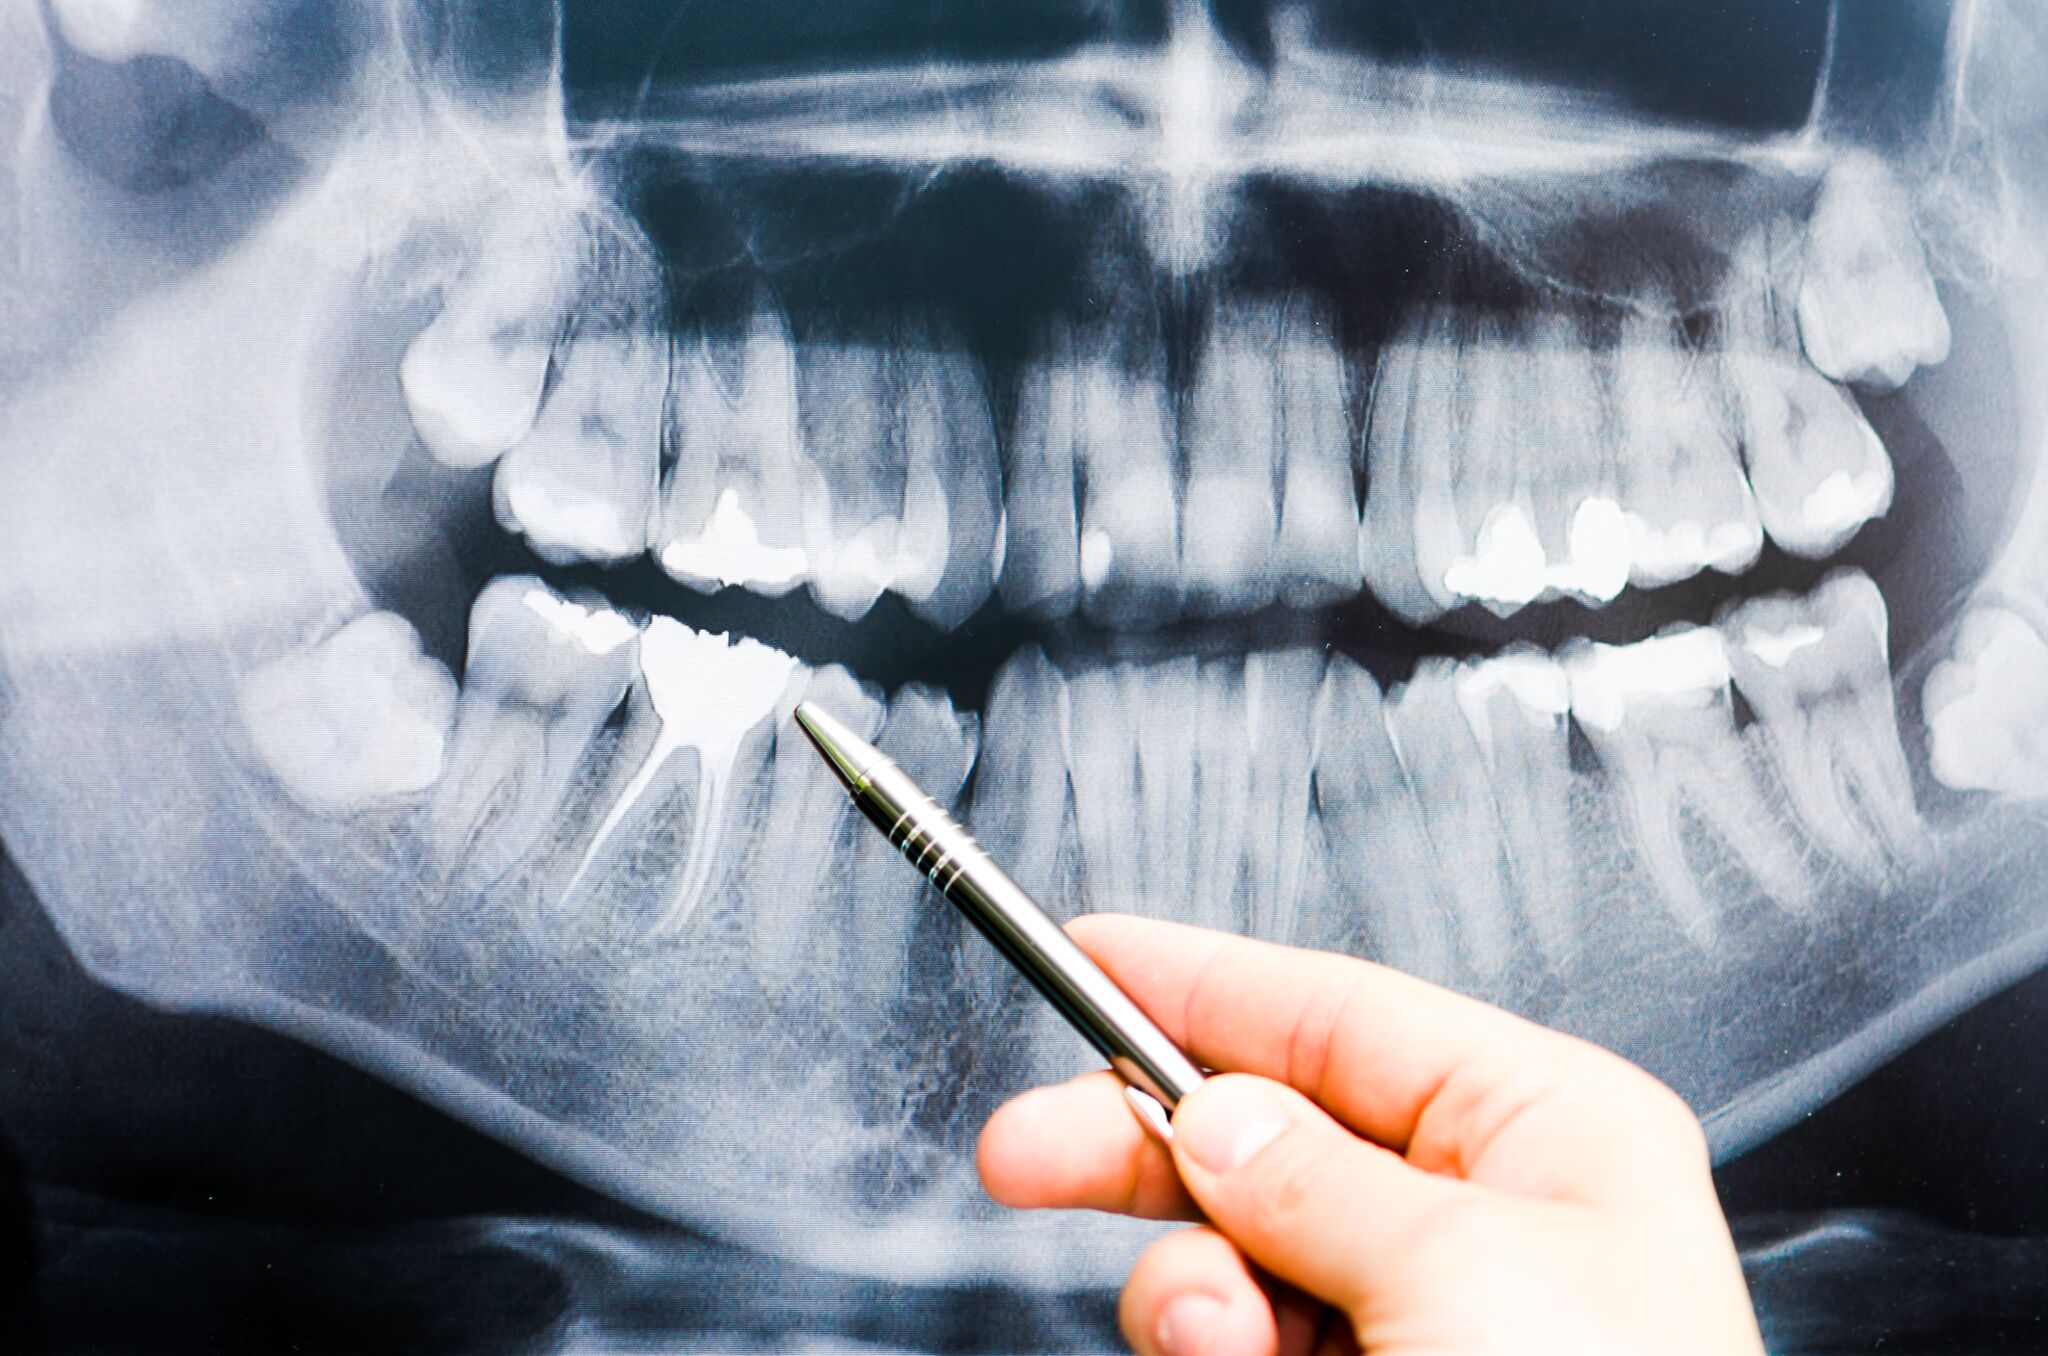

To grasp the reasons behind that startling yet harmless pop, one must first delve into the complex anatomy of the temporomandibular joint. This intricate joint connects the jawbone to the skull, enabling essential functions such as chewing, speaking, and even yawning. The TMJ is a remarkable feat of engineering, composed of cartilage, ligaments, and a disc that cushions the jawbone against the skull. Its multifaceted movements allow for a wide range of motion, but these very complexities can also lead to some unusual auditory experiences.

Another reason for jaw popping relates to the articular disc within the TMJ. This structure acts as a shock absorber, allowing smooth motion between the bones. If there’s a slight misalignment, the disc may momentarily slip out of place during movement and then return, creating a clicking or popping noise. Interestingly, this experience can happen without leading to discomfort, suggesting that the joint, while perhaps functioning imperfectly, is not inherently dysfunctional.

- Arthritic Changes: Although linked with discomfort in some cases, mild arthritic changes may show no pain but can lead to joint sounds due to the wear of cartilage.